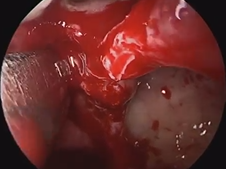

Microdirect Laryngoscopy and CO2 Laser Total Vestibulectomy for Pyolaryngocele

- Date : 01/01/2020